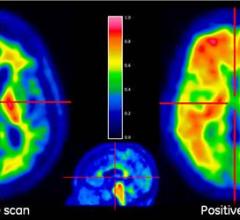

One of the hottest topics in current Alzheimer’s research is brain scans that visualize tau pathology in living people. With the advent of positron emission tomography (PET) tracers that label neurofibrillary tangles, researchers are now able to "see" and quantify both hallmark pathologies defined by Alois Alzheimer in 1906: amyloid plaques and tau tangles. Tau tracers dominated the agenda when 340 researchers convened in Miami Beach, Florida, recently to debate the current edge in human amyloid imaging.